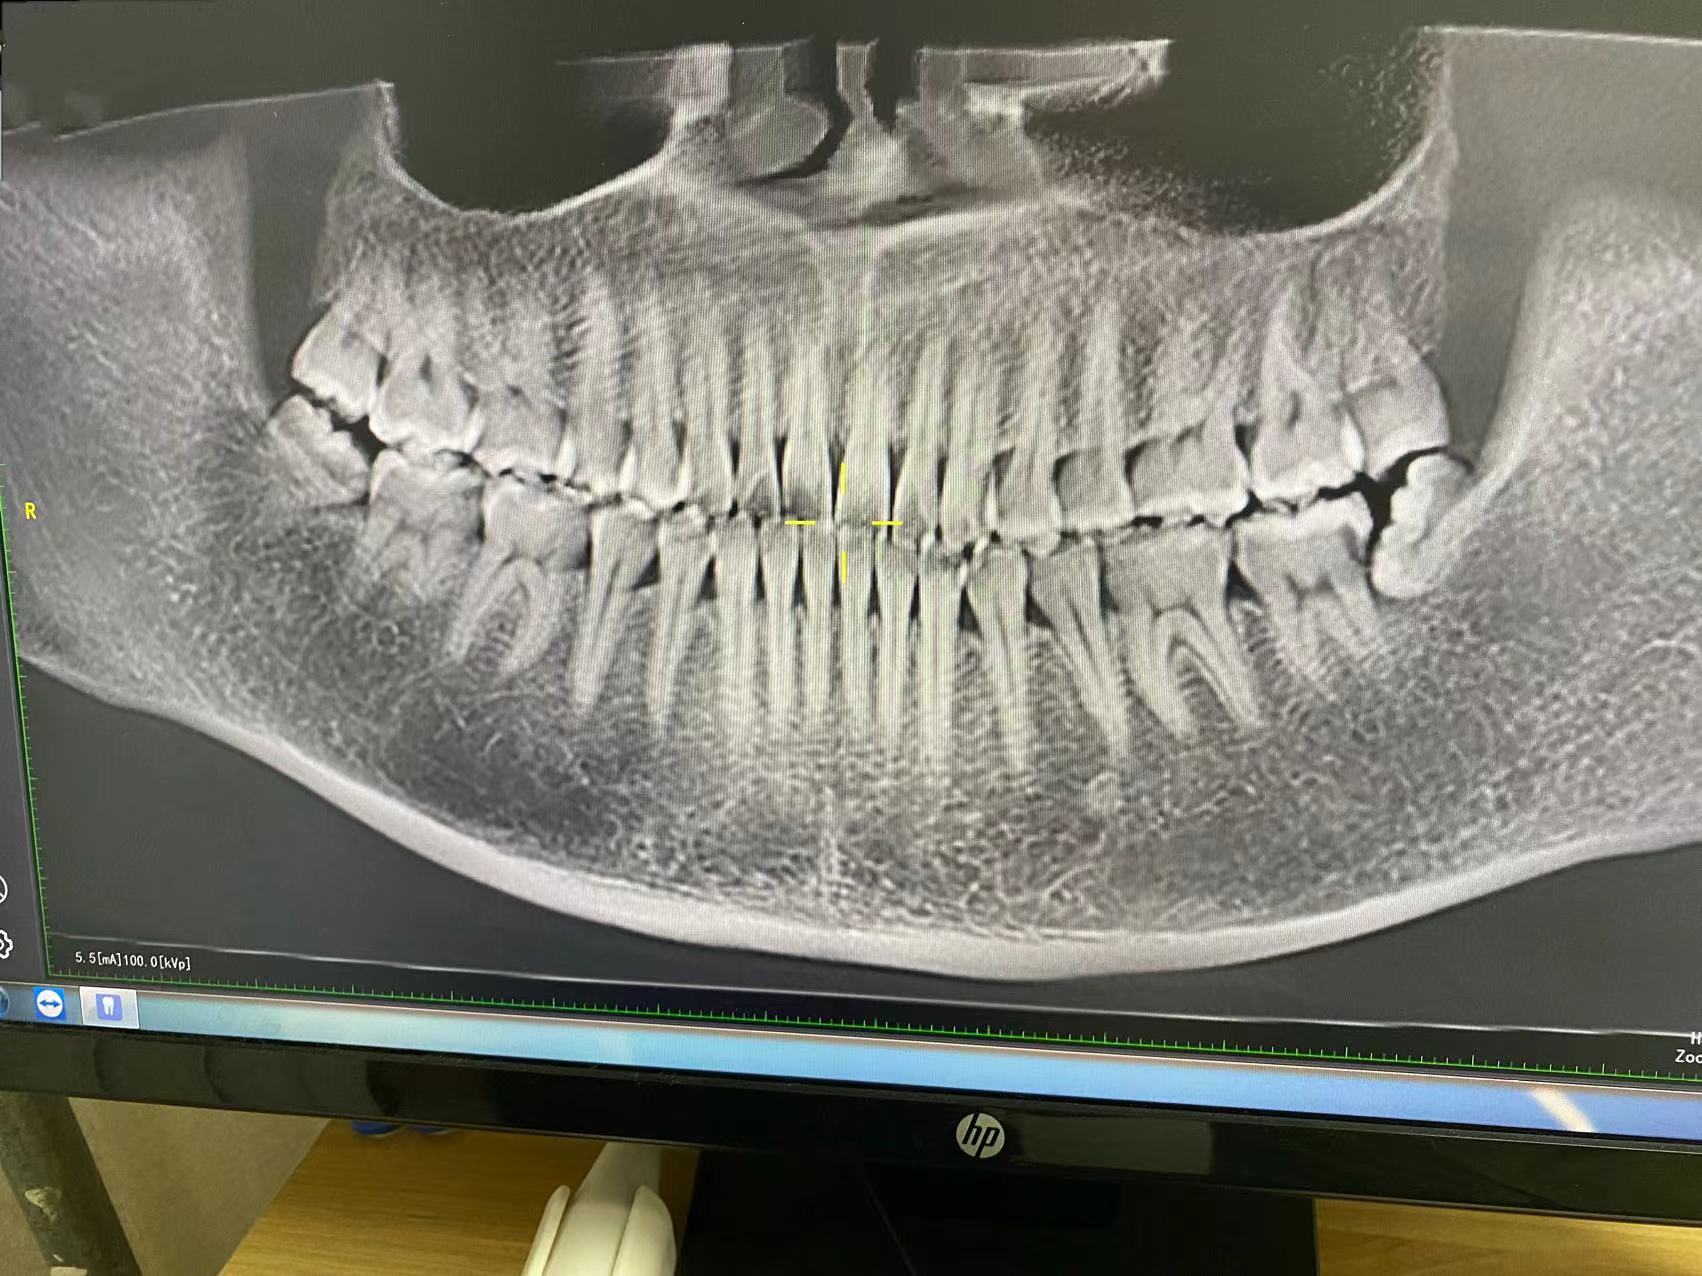

洗完牙,拍了照片,发现了我的四颗智齿,医生建议全部拔掉,从照片上来看,有颗确实长歪了,把前面的牙齿都顶了个洞。

先拍了照片,医生说先拔左侧的智齿,它把前面的牙弄坏了,比较着急。

拔智齿,真的特别特别疼,我左下侧的智齿是阻生齿,斜着长的,先打了麻药,医生试了试,说不能直接拔,需要切开牙龈,把牙齿切成2瓣,再一个个个取出。